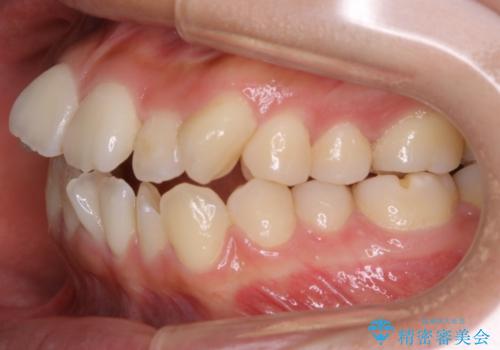

- 上下の歯のガタつきを主訴にご来院されました。

前歯部に特にガタつきが見られ、正中もズレている状態でした。

矯正装置の希望がインビザラインだったため、マイクロインプラントを併用し、奥歯から順に遠心移動をかけていくことにより非抜歯でも主訴のガタつきを治すことができました。

マウスピースとマイクロインプラントを組み合わせることで、抜歯をしなくても歯並びを治すためのスペースを作ることができます。奥歯から順に移動させていくので前歯に変化が出るまでには時間がかかりますが、その分健康な歯を抜歯することなく理想的な歯並びを手に入れることができます。